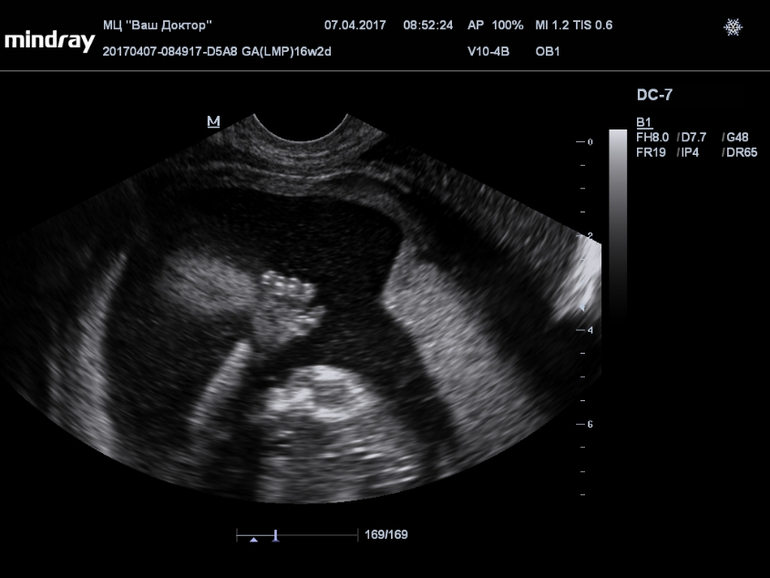

Пол малышаВсе 16 недель была просто уверенна, что в домике живет сыночка, а тут на УЗИ огорошили, что у нас там девица-красавица! Я конечно прибываю в небольшом шоке, но БЕЗУМНО этому рада!!!!!

Записали нам диск, все выходные пересматривала, сделала несколько фото, что скажете?

(фото под кат)...